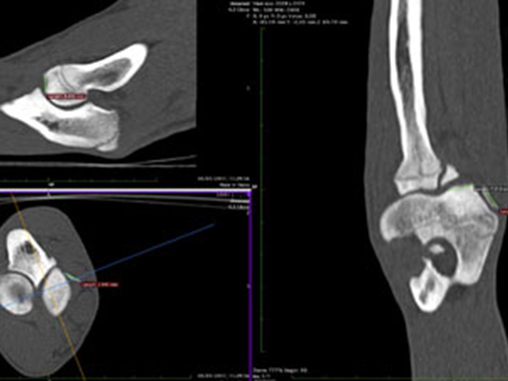

CT scanning is as rapid as routine radiography and in many cases quicker and has proved to be invaluable to the improved diagnostics for orthopaedic disease and injuries for cats and dogs, especially in elbow dysplasia and patella luxation where the improved diagnostics are making our treatments more accurate with improved functional outcomes and reduced complications.